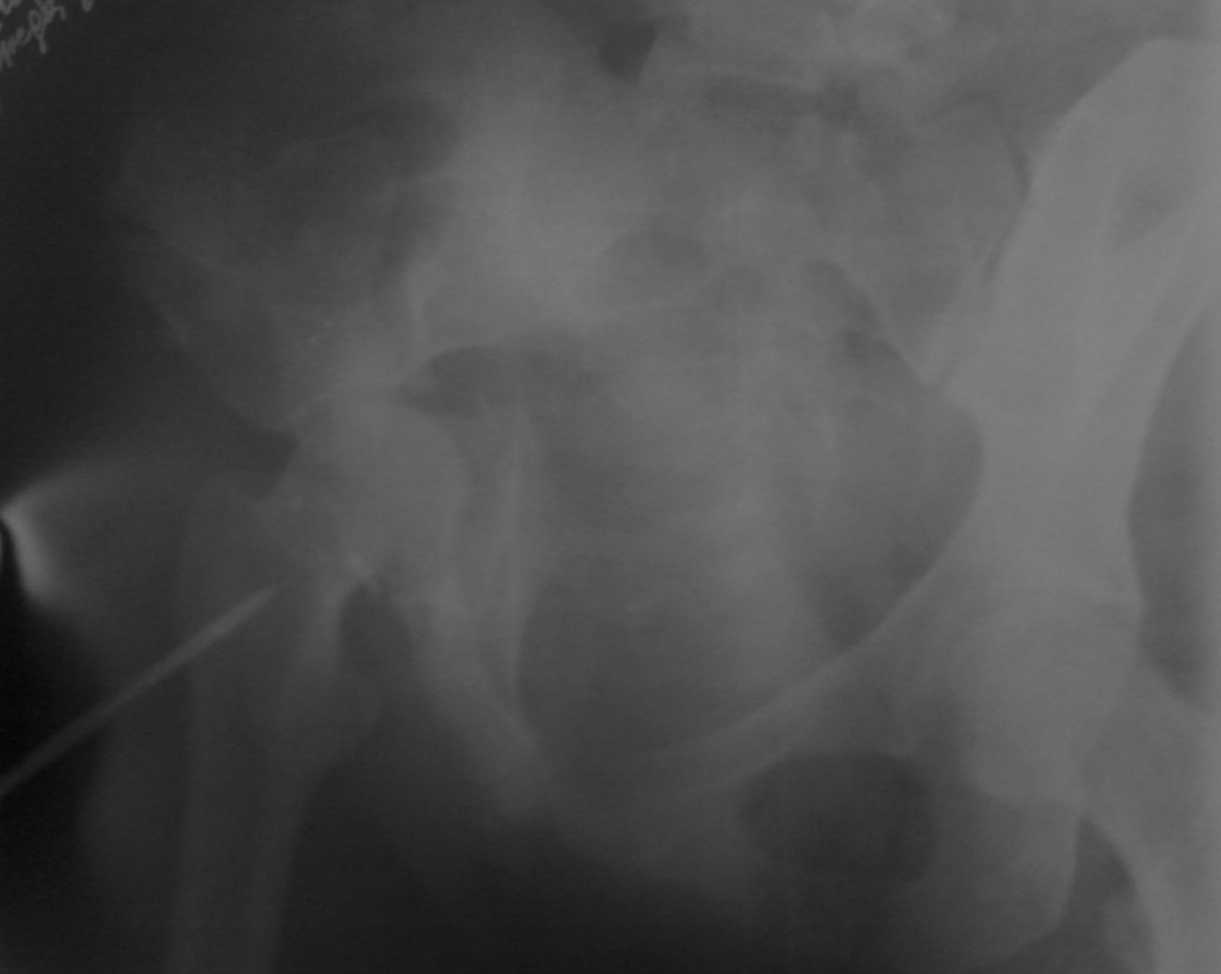

Больная М. 31 год ДТП 12.07.07 боковой удар, в наше отделение поступиа на 10 сутки , наложено скелетное вытяжение за большой вертел.

Помогите определить дальнейшую тактику лечения . Вести консервативно и готовить к протезу через 6 меяцев или попытаться собрать все при помощи пластинок. Заранее спасибо.

Без стандартных проекций фас, inlet, Judet нормального качества о тактике можно только гадать Похоже на высокий двухколонный перелом, пока нужно как минимум увеличить грузы на тяге по оси бедра (до 12-15 кг, вытяжение за мыщелки бедра)

По представленной проекции трудно отличить высокий двухколонный перелом от высокого перелома передней колонны с задним полупоперечником. В первом случае можно добиться репозиции тягой за мыщелки бедра,

обязателен рентген -контроль (лучше КТ) в процессе репозиции. При отсутствии ступенеобразной деформации, даже при наличии расширения сустава, гиперпокрытия можно ожидать хороший функциональный результат.

Во втором случае (задний полупоперечник), либо при сохраняющейся ступенеобразной деформации консервативное лечение будет скорее всего не эффективно, но может облегчить последующее

эндопротезирование.

Стержень из вертела лучше убрать, как правило он находится в отслаивающей гематоме, тем самым увеличивая риск ее нагноения, помощи от него мало, но можно ограничить себя в плане выбора доступа при оперативном лечении и получить проблемы при эндопротезировании.

При имеющемся стоянии отломков ожидать сращения ни через 6 месяцев ни через год не приходится, поэтому, в случае эндопротезирования в эти сроки вертлужный компонент может стоить как хороший автомобиль, да и операция очень усложняется.